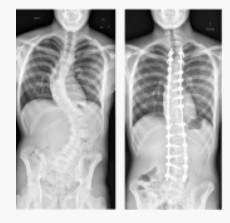

• Scoliosis is a complex condition that varies from individual to individual.

• While the curvature of the spine is a characteristic feature, the curve’s angle, intensity, progression and imbalances it causes vary from person to person.

• Scoliosis can affect the ability to run in a few cases due to the following reasons: